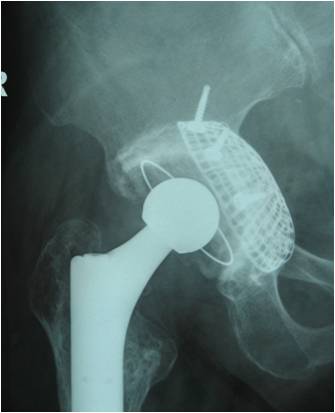

19髋中,18髋的髋臼假体稳定,未发现臼杯在垂直和水平方向大于1mm的移位,也未发现髋臼假体外展角的改变(图1-3)。有1例PaproskyⅢB型患者出现金属网及髋臼杯明显移位等影像学松动表现:术后12月随访时,髋臼上移16.8mm,内移4.7mm;术后28月时,髋臼上移22.7mm,内移5.8mm,髋臼假体外展角较术后减小2.2°(图4-6)。但患者髋关节疼痛不明显,日常生活中能无需手杖独立行走,拒绝再次翻修手术。

图1 全髋关节置换术后无菌松动,髋臼PaproskyⅢA型骨缺损

图2 术后6周,臼底缺损用金属网封闭

图3 术后36月 异体骨整合良好